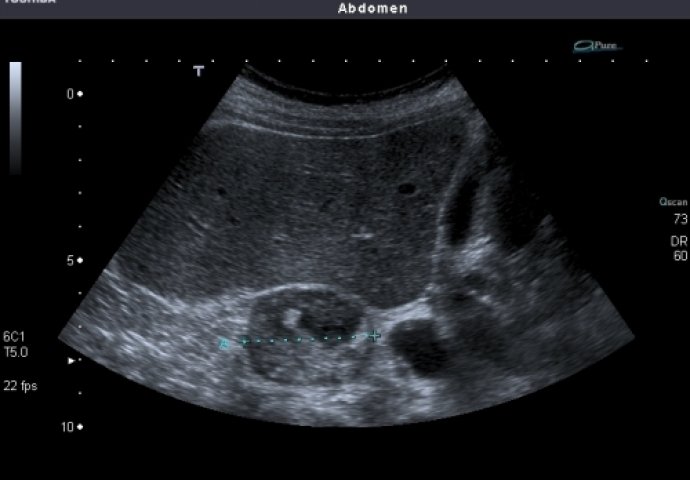

Za dijagnosticiranje poremećaja nadbubrežne žlijezde, lekari mogu preporučiti različite testove, uključujući analize krvi i urina, kao i slikovne preglede. Tretman može varirati od hormonske terapije do hirurških zahvata, zavisno od specifičnog poremećaja i njegovih uzroka. U nekim slučajevima, promjene u ishrani i načinu života takođe mogu igrati ključnu ulogu u poboljšanju funkcije nadbubrežne žlijezde.